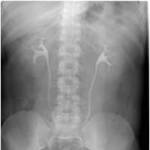

Radiograph #1

Urinary Tract

Identify: Minor calyx, major calyx, renal pelvis, ureter, left kidney, right kidney, ala sacrum.